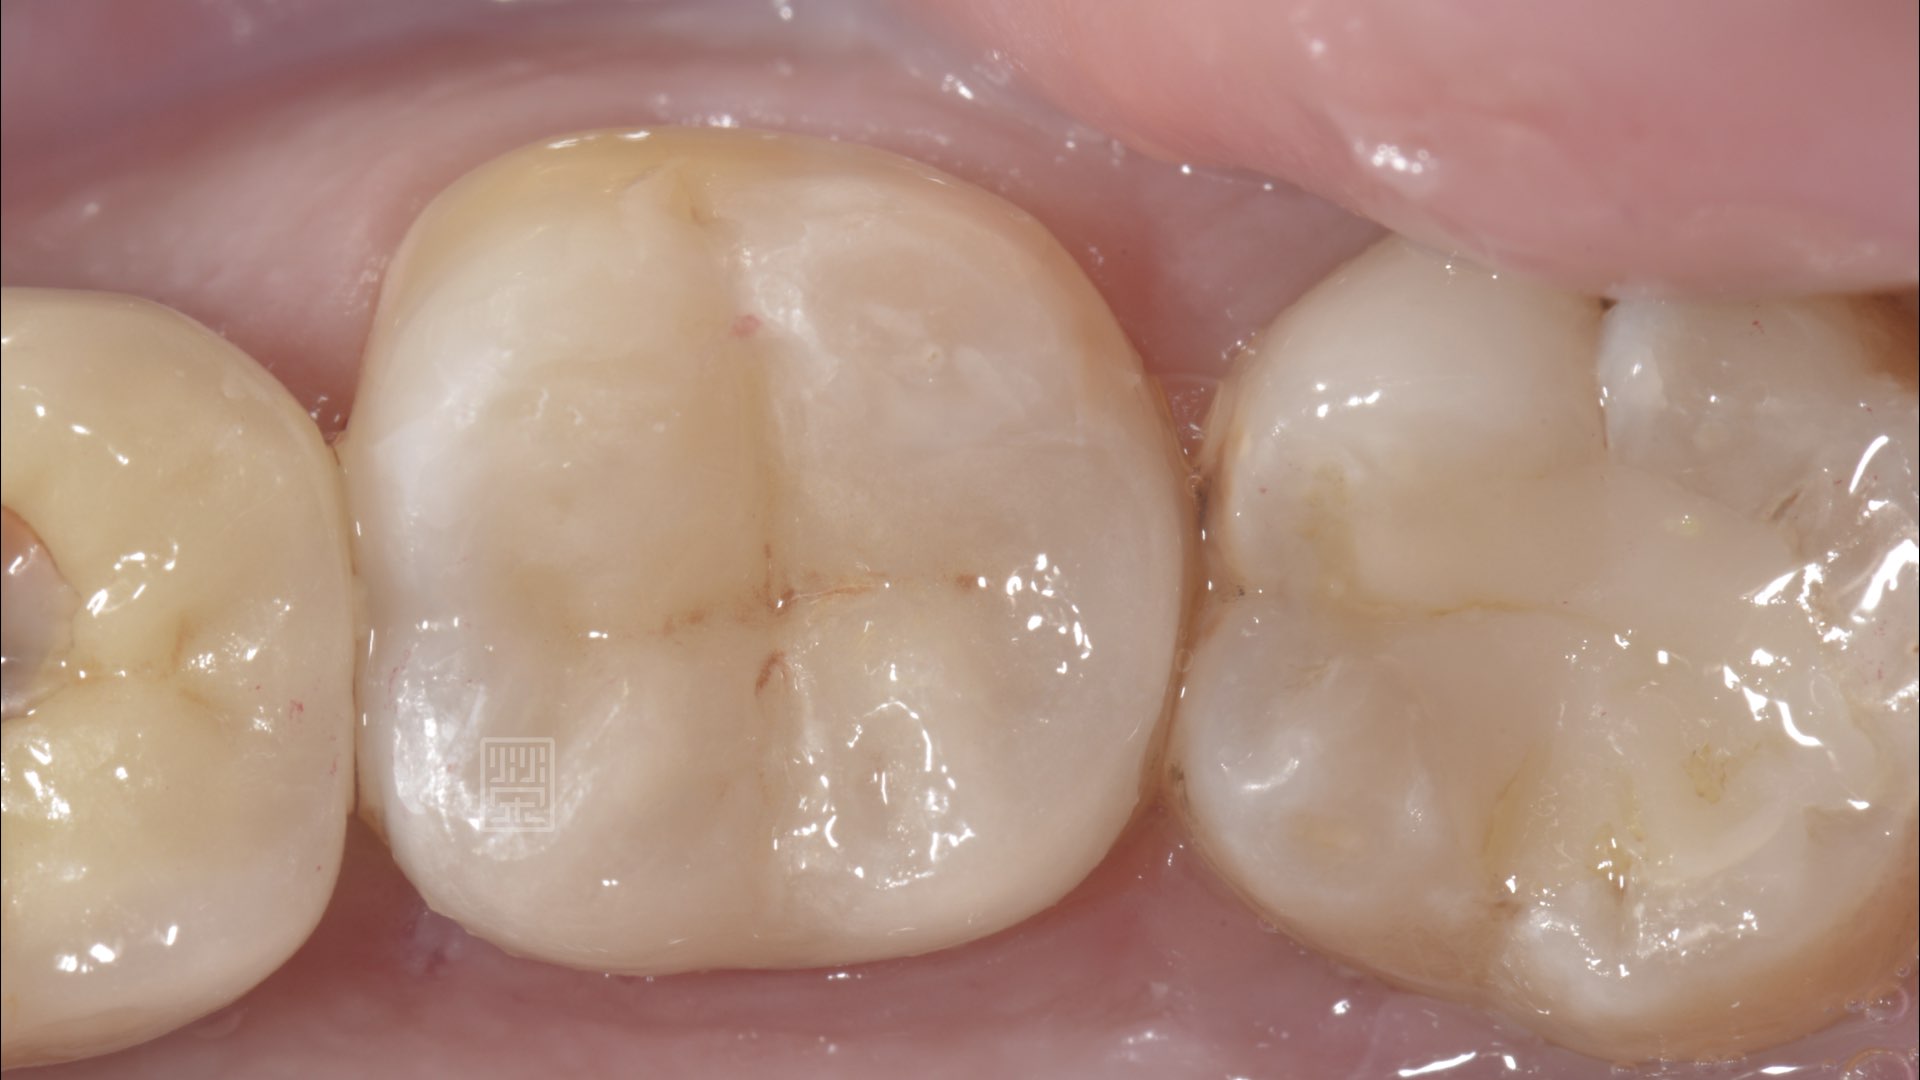

全瓷嵌體修復